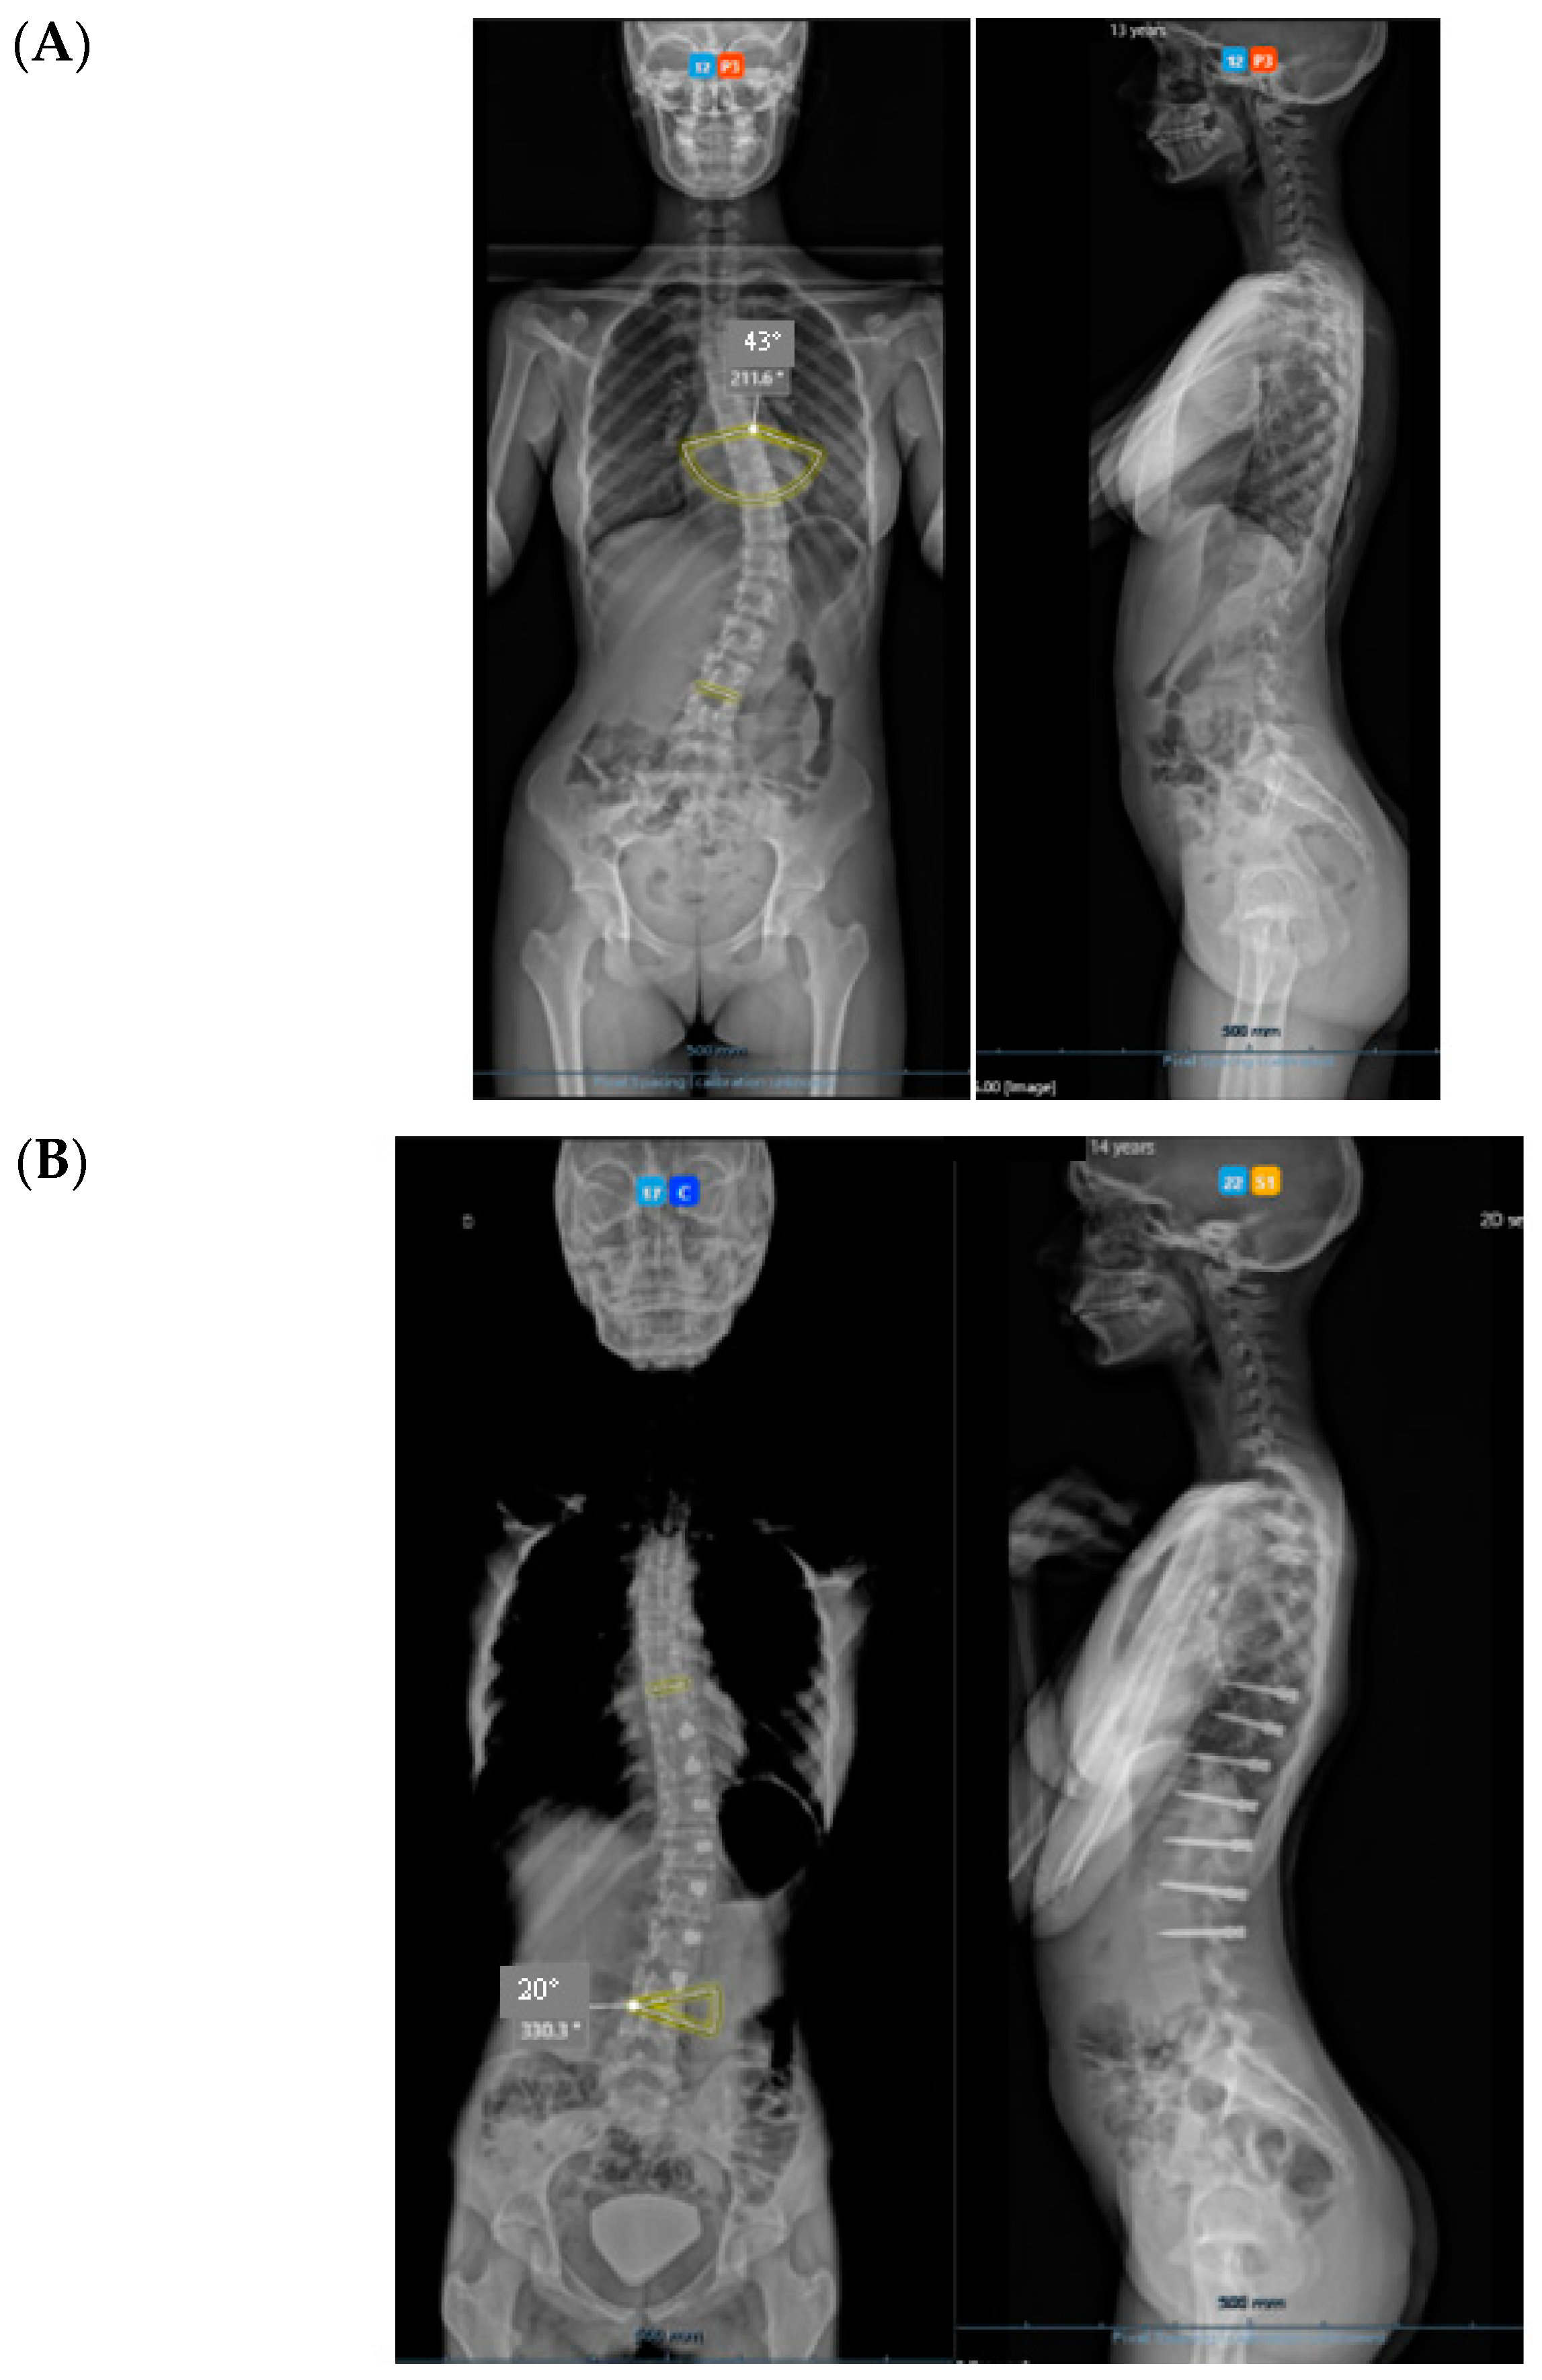

All three cases were thoracolumbar scoliosis (Lenke 5C) with an apex between T12 and L1 (Figure 3, Figure 4 and Figure 5).

Figure 3.

A 14-year-old adolescent. (A) Pre-op. (B) Immediate post-op. (C) One-year follow up.

Figure 4.

A 13-year-old adolescent. (A) Pre-op. (B) At 6-month follow up.

Figure 5.

A 14-year-old adolescent. (A) Pre-op. (B) At 6-month follow up.

As far as skeletal maturity is concerned, two cases were Sanders 3 (Risser 1 and 0) and one case was Sanders 5 (Risser 4).

3. Results

All cases have progressed well with improvement of the curvatures with growth (Table 1) both in the coronal and sagittal alignment. At the 6-month FU, there was a mean 67.5% (34.8°) improvement in the main Cobb angle, but at 1 y, the oldest case over-corrected, and this was clinically noted by the girl, who pointed out that her flank symmetry had recently inverted (from one side to the other) after being symmetrical for some time (Figure 6).

Regarding the sagittal profile, we have looked at three different segments—T1–T9, T10–L3, and L3S1. In this 6-month period, the proximal segment in these three cases had increased kyphosis by 7.7°; the intermediate segment had increased lordosis by 10.9°; and the distal lumbar segment had decreased lordosis by 13.6°. However, in the only case that underwent tether release due to coronal over-correction, it is interesting that the thoracic kyphosis increased, the intermediate lordosis decreased, and the distal lumbar lordosis increased post-operatively; as such, spinal sagittal balance was well-maintained.

Concerning de-rotation, we can assess the apical vertebral rotation on the pre-operative radiograph as a Cobb grade +3 (Nash–Moe 50%) that improved to a Cobb grade +1 (Nash–Moe of 0%) in the last FU film (Figure 7) one year later.